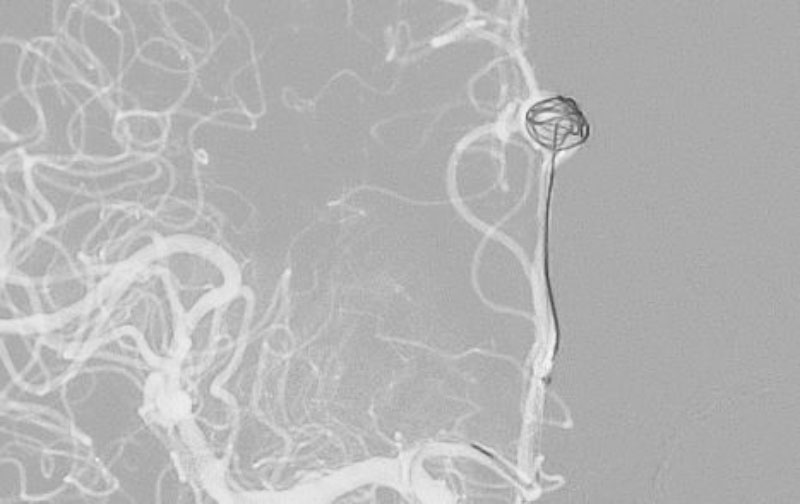

No.1596 手術後

くも膜下出血

左中大脳動脈瘤破裂

40代

救急外来